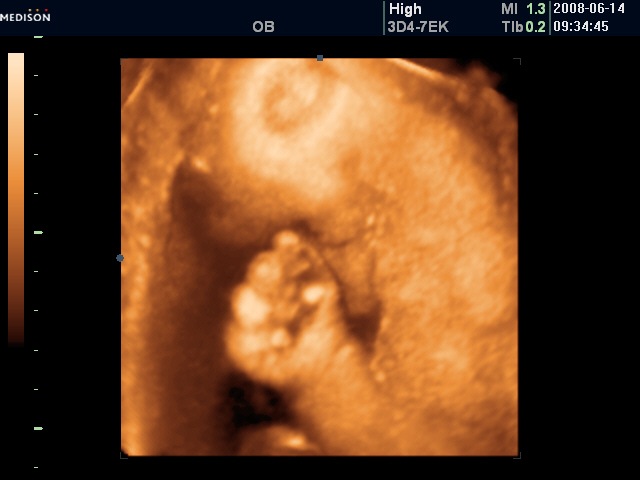

No for the fun, the sonogram. Yang wanted to double check that it was indeed a girl and indeed that has been confirmed. The doctor checked the baby’s development and it is right on tract. Almost right in the middle of normal. They then took some pictures. Here’s the future Beijing allio girl:

The feedback is the nose is bigger than they typical Chinese but I suspect not bigger than the typical allio.